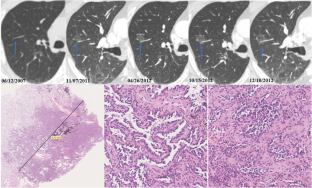

Between June 2012 and June 2019, 95 resected SSNs with preoperative long-term follow-up were enrolled in this retrospective study. SSN detection and segmentation were performed on preoperative follow-up CTs using the deep learning–based Dr. Wise system. SSNs were categorized into invasive adenocarcinoma (IAC, n = 47) and non-IAC (n = 48) groups; according to the interval change during the preoperative follow-up, SSNs were divided into growth (n = 68), nongrowth (n = 22), and new emergence (n = 5) groups. We analyzed the cumulative percentages and pattern of SSN growth and identified significant factors for IAC diagnosis and SSN growth.

The mean preoperative follow-up was 42.1 ± 17.0 months. More SSNs showed growth or new emergence in the IAC than in the non-IAC group (89.4% vs. 64.6%, p = 0.009). Volume doubling time was non-significantly shorter for IACs than for non-IACs (1436.0 ± 1188.2 vs. 2087.5 ± 1799.7 days, p = 0.077). Median mass doubling time was significantly shorter for IACs than for non-IACs (821.7 vs. 1944.1 days, p = 0.001). Lobulated sign (p = 0.002) and SSN mass (p = 0.004) were significant factors for differentiating IACs. IACs showed significantly higher cumulative growth percentages than non-IACs in the first 70 months of follow-up. The growth pattern of SSNs may conform to the exponential model. The initial volume (p = 0.042) was a predictor for SSN growth.

IACs appearing as SSNs showed an indolent course. The mean growth rate was larger for IACs than for non-IACs. SSNs with larger initial volume are more likely to grow.